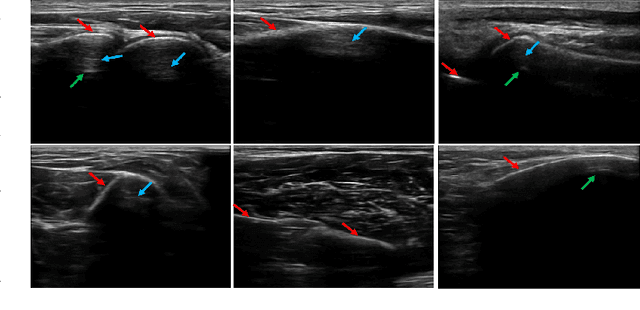

Abstract:Bone surface delineation in ultrasound is of interest due to its potential in diagnosis, surgical planning, and post-operative follow-up in orthopedics, as well as the potential of using bones as anatomical landmarks in surgical navigation. We herein propose a method to encode the physics of ultrasound propagation into a factor graph formulation for the purpose of bone surface delineation. In this graph structure, unary node potentials encode the local likelihood for being a soft tissue or acoustic-shadow (behind bone surface) region, both learned through image descriptors. Pair-wise edge potentials encode ultrasound propagation constraints of bone surfaces given their large acoustic-impedance difference. We evaluate the proposed method in comparison with four earlier approaches, on in-vivo ultrasound images collected from dorsal and volar views of the forearm. The proposed method achieves an average root-mean-square error and symmetric Hausdorff distance of 0.28mm and 1.78mm, respectively. It detects 99.9% of the annotated bone surfaces with a mean scanline error (distance to annotations) of 0.39mm.